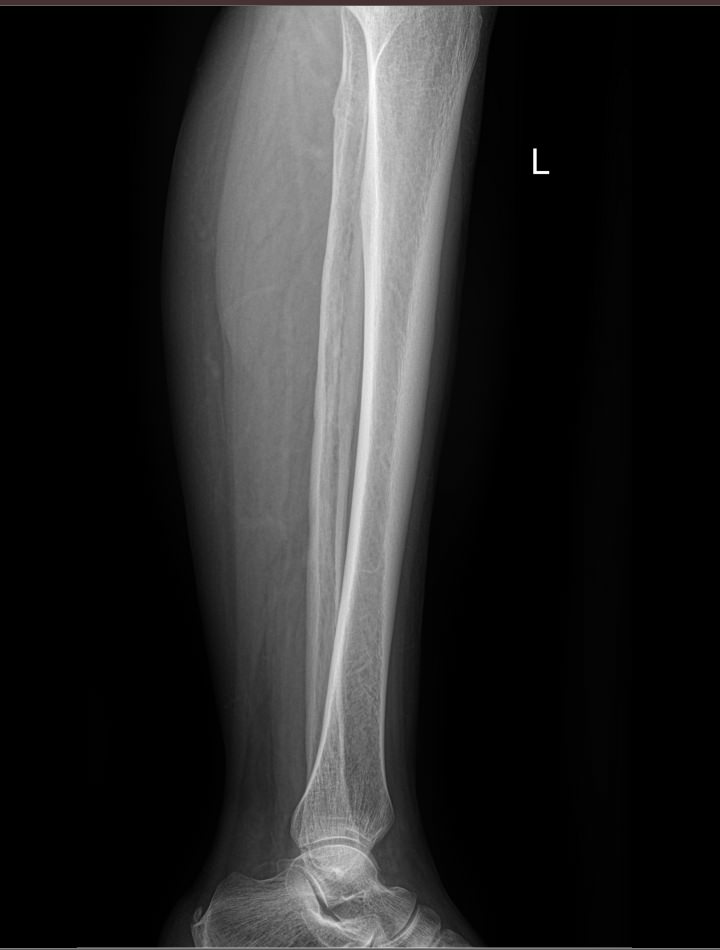

В области голени располагаются 2 кости ― большая и малая берцовые. Разные по толщине, они, тем не менее, составляют крепкую конструкцию, позволяющую человеку ходить и бегать, нести вес тела и дополнительный груз. Повреждение и травмы голени, а также прилежащих суставов, коленного и голеностопного, резко уменьшает мобильность человека. Хронические процессы, начинаясь незаметно, постепенно приводят к тому же.

Рентген является простым, доступным, высокоинформативным и безболезненным видом диагностики патологий костной ткани, в том числе ― костей голени. А современная цифровая аппаратура позволяет выполнять снимки настолько часто, насколько этого требует заболевание, не превышая допустимую дозу облучения.

На снимке рентгенолог последовательно просматривает все образования голени и описывает их изменения:

• Новообразования: местоположения, затрагивают ли костную ткань;

• Диафизы и эпифизы костей: наличие перелома, его смещения, костной мозоли, их месторасположение и соответствие срокам травмы;

• Костная ткань: очаги разрежения, уплотнения, размягчения, склерозирования и других изменений, в том числе послеоперационных;

• Надкостница: истончение, обызвествление;

• Входящий в снимок сустав: есть ли изменения, типичные для травмы или воспаления;

• Мягкие ткани: есть ли отек и инородные тела.

Специальная подготовка не нужна. Пациент снимает одежду с нижней половины туловища, оставаясь в белье, надевает защитную накидку, и ложится на снимочный стол, как показывает рентгенолаборант. Обычно снимок делают в прямой проекции, то есть нога лежит прямо. Но если в направлении врач указывает боковую проекцию, пациент ложится на бок, а исследуемую ногу немного сгибает. В обоих случаях здоровая нога отводится в сторону. Также в направлении указывается, какой сустав должен войти в снимок ― коленный или голеностопный.